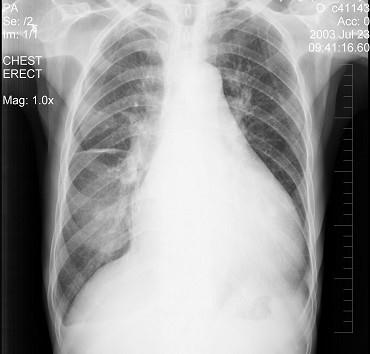

问题 患者女性,70岁,胸闷、气逼数年,无明显发热、胸痛,如图最可能的诊断是 ( )

选项 A.心包积液并右水平裂积液 B.心包积液并右下肺炎 C.心包积液并右斜裂积液 D.心包积液并右双叶间裂积液 E.气胸

答案 D